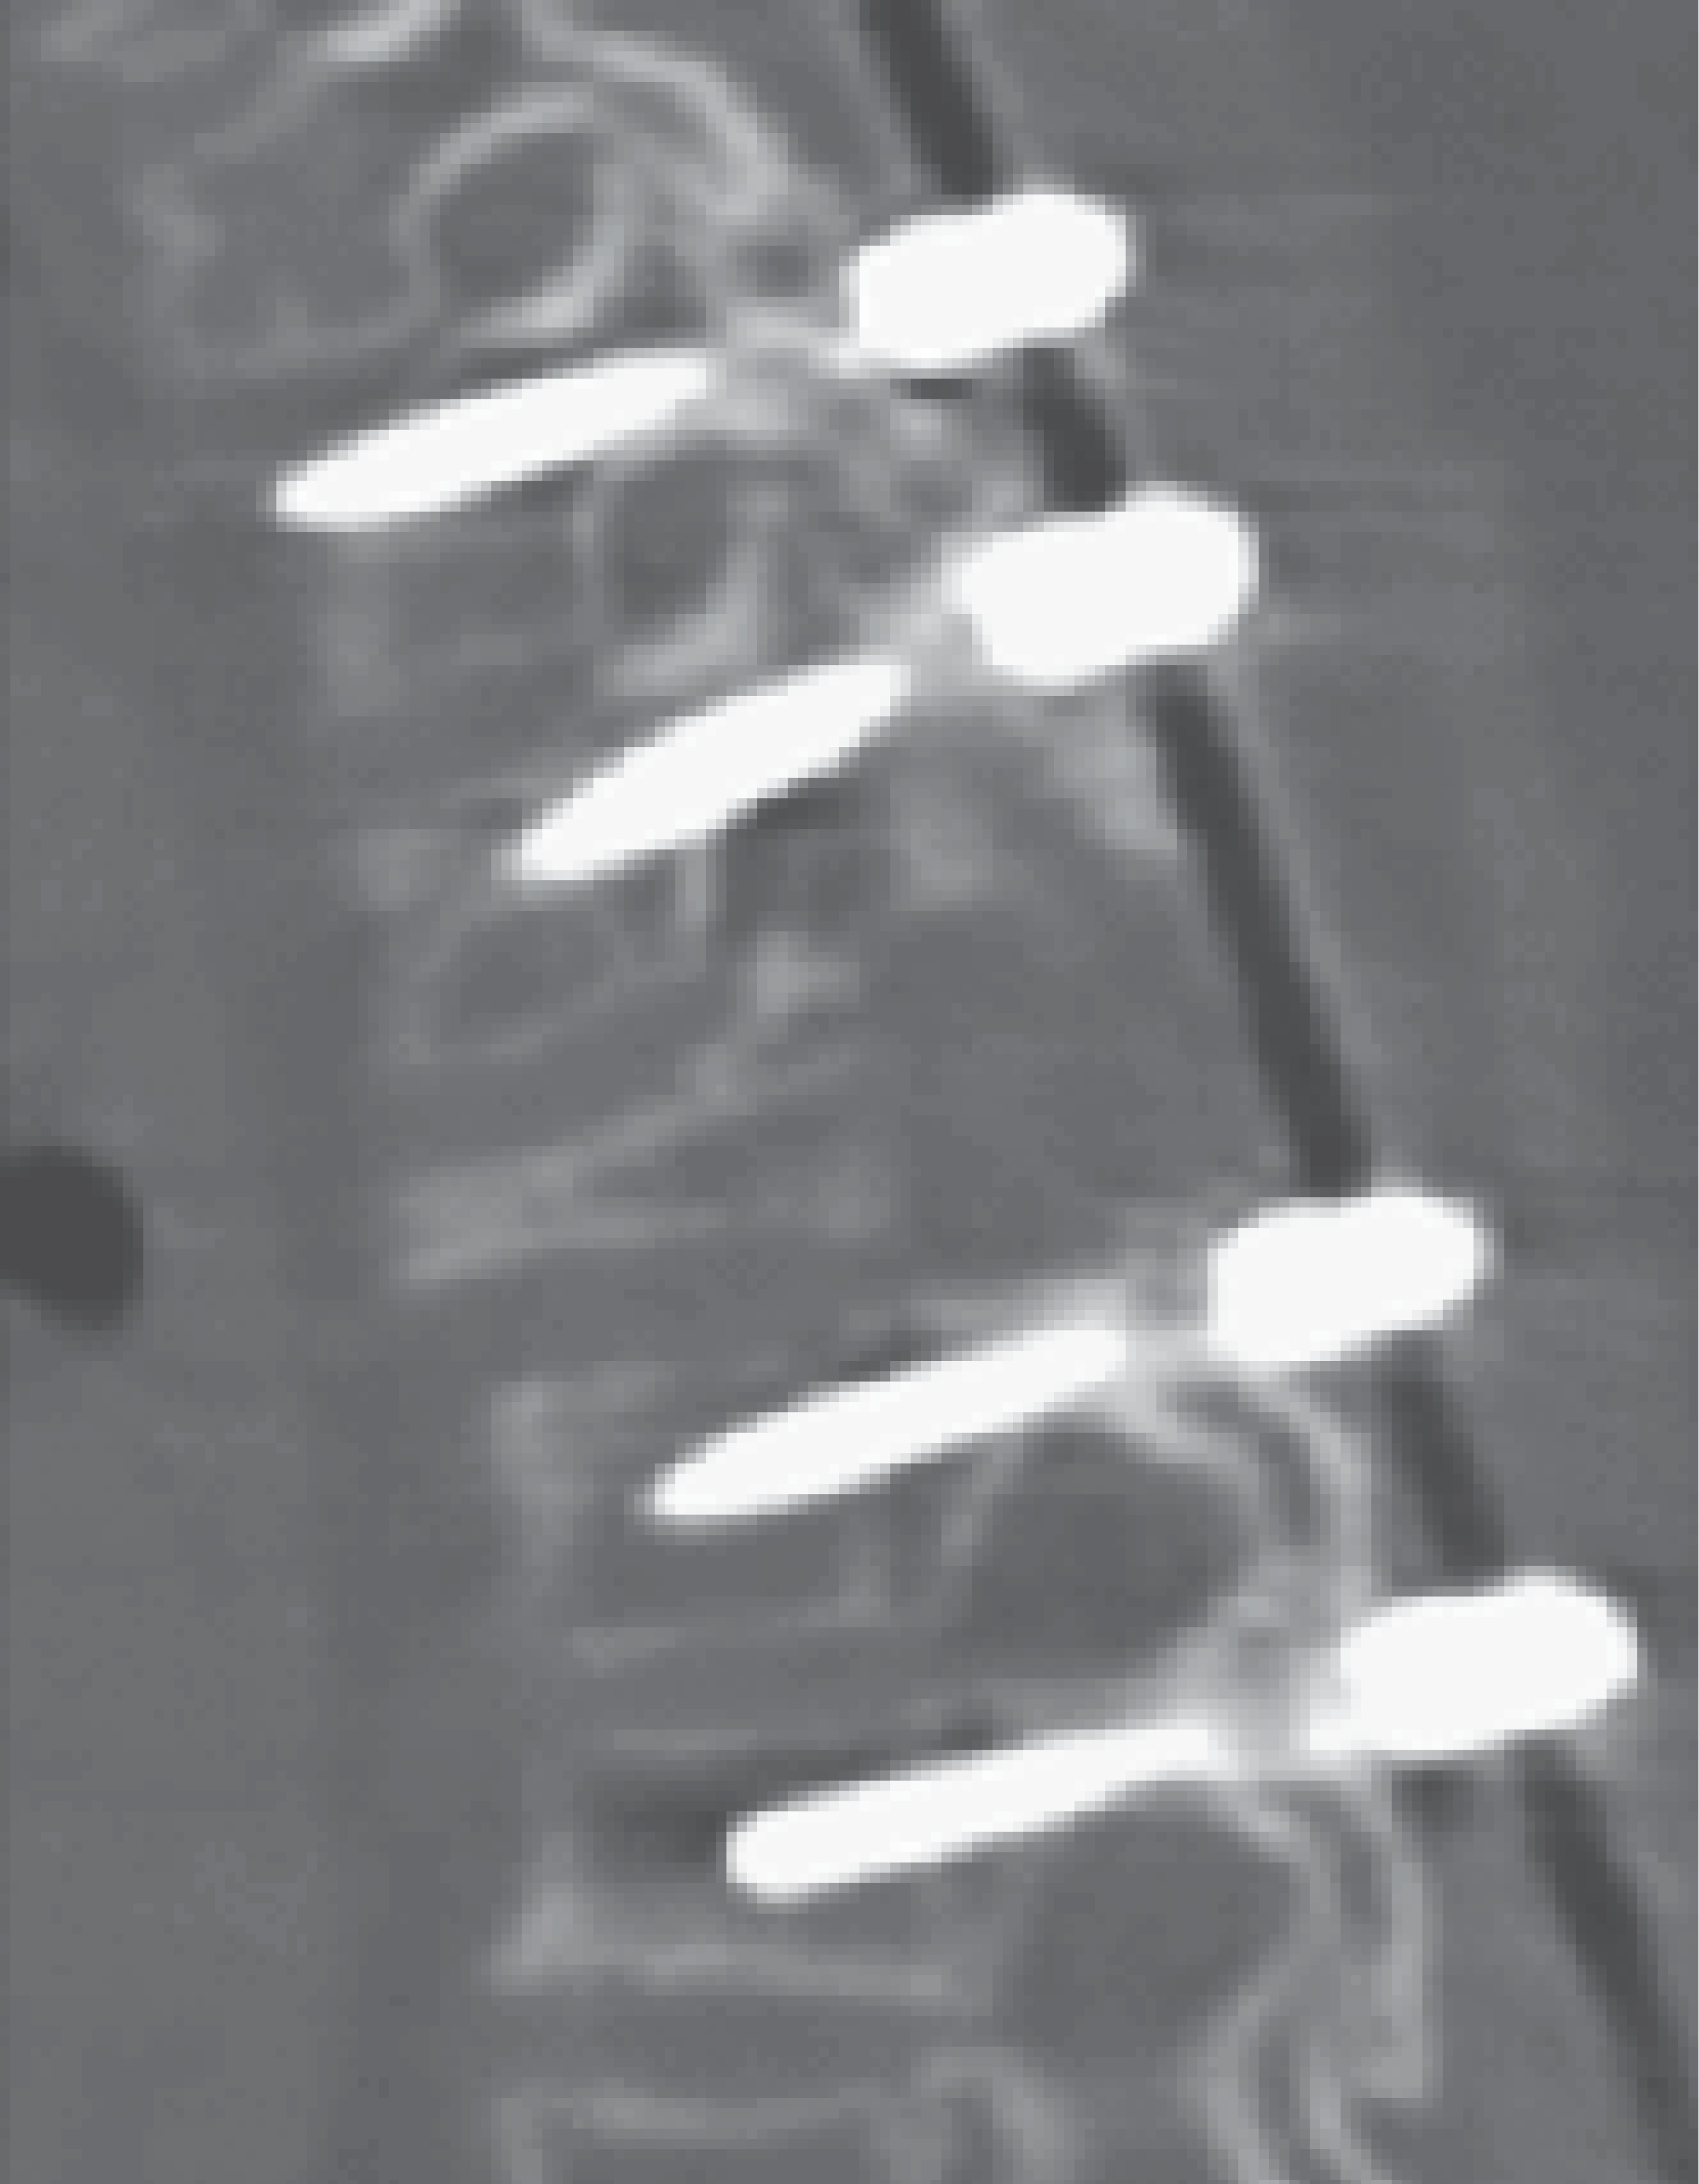

A su ingreso se encuentra con fuerza muscular 1/5 desde L 2 a distal, hiperreflexia rotuliana y aquílea, clonus, Babinski bilateral, hipoestesia de T4 a distal, control de esfínteres presente. Motivo por el cual se decide realizar instrumentación pedicular T2-T3, puenteo a T4 y fijación distal T5-T6 más resección intralesional del tumor (Figura 3). El implante seleccionado fue un sistema facetario/pedicular tipo Axon. Se efectúa planeación quirúrgica digital mediante el uso de tomografía axial computarizada simple (TAC) con reconstrucción en 3D usando el programa OsiriX para valorar sitio de colocación de tornillos facetario/pedicular (Figura 4). Se ingresa a la unidad de cuidados intensivos procedente de quirófano por iniciar retención de CO2 importante, permanece en dicha unidad durante 24 horas y se egresa a hospitalización al área de ortopedia pediátrica.

El resultado postquirúrgico lo observamos en la Figura 3 donde se muestra una tomografía en corte sagital con presencia de tornillos facetario/pedicular en los niveles ya mencionados con puenteo de T4, lo que permite resección quirúrgica del tumor con descompresión del conducto medular.